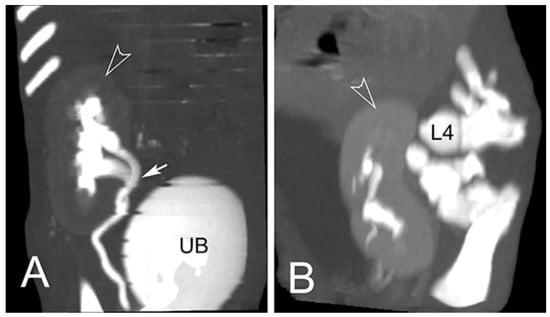

| 1 * | None | partial aplasia of L4, quite complete aplasia of the vertebral canal of L5, partial aplasia with absence of the vertebral canal of L6; scoliotic deviation toward the right. | partial aplasia of S1 with absence of the vertebral canal. | Coccygeal vertebrae: no visible abnormalities other abnormalities: duplication of the first tract of the ureters; caudal dislocation of the left kidney with a dorso-medial bended shape and some cortical small cists |

| 2 * | None | the lumbar tract showed a lordotic and scoliotic curvature; L2-L3-L4 were irregularly fused and L3-L4 without a vertebral canal; L5 and L6 were present only as a bud of the body with the agenesia of the vertebral arch. | S1 and S2 missed the vertebral canal and were irregularly articulated | Coccygeal vertebrae: only the first five metameric were visible |

| 3 * | None | the lumbo-sacral junction showed a slight lordotic curvature; L6 missed the vertebral canal. | S1 was present only as a bud of the body with the agenesia of the vertebral arch | Coccygeal vertebrae: Only four coccygeal vertebrae were present. |

| 4 ** | T14 was partially fused with L1. | L1 was partially fused with T14 and its body was wedge shaped (hemi vertebra) L2 had a dysplastic vertebral canal and was partially fused with L3; the residual lumbar vertebrae were present only as a bud, without a vertebral canal and with a scoliotic curvature toward the left | S1 was present as a small bud, the remnant were partially fused and with a kyphotic curvature. | Coccygeal vertebrae: Visible until the Co15 with some hemi vertebrae. Other abnormalities: Partial fusion of the left 13th and 14th ribs; the pelvis was tilted toward the left; severe hyper extension of the left knee with inversion of the normal angle. |

| 5 ** | Visible T16 with a complete aplasia of the vertebral canal. | vertebrae L1 had only a slight mineralization of the body and the remnant (L2-L6) were present only as a bud of the body with a complex lordotic-scoliotic curvature toward the right. | the body of S1 was partially fragmented and without the vertebral canal; S2 was visible only as a small bud; no other sacral vertebrae were visible. | Coccygeal vertebrae: The coccygeal vertebrae were absent. Other abnormalities: both the knees had an inverted angle. |

| 6 ** | Visible T15 | partial aplasia of L2 with an incomplete vertebral canal; L3 without the vertebral canal and a right fragmented lateral process; the remnant lumbar vertebrae (L4-L6) were present only as a bud of the bodies and with a lordotic curvature. | partial dysplasia of the body of S1 with a not fused cranio-ventral portion of the body and without the vertebral canal. | Coccygeal vertebrae no visible abnormalities. |

| 7 ** | None | partial aplasia of L4 without the vertebral canal; L5 and L6 were present only as a small bud of the bodies. | no visible abnormalities | Coccygeal vertebrae no visible abnormalities Other abnormalities Severe hyper extension of both the knees and the tarsi. |

| 8 ** | None | L1 was dysplastic with bifid dorsal process and the vertebral canal communicating with the dorsal soft tissues of the lumbar tract; absence of the vertebrae from L2 to L4; L5 and L6 partially fused and with aplasia of the vertebral canal. | Sacral vertebrae S1 and S2 were partially fused and irregularly fragmented without the vertebral canal. | Coccygeal vertebrae no visible abnormalities. |